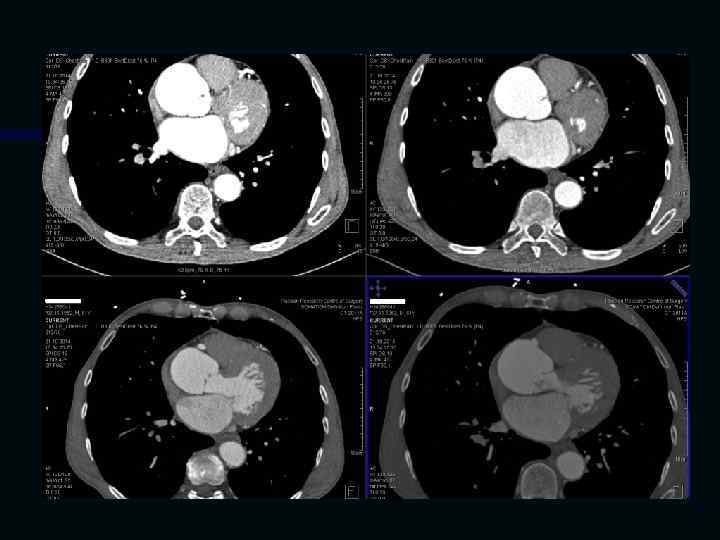

Исследование сосудов грудной клетки